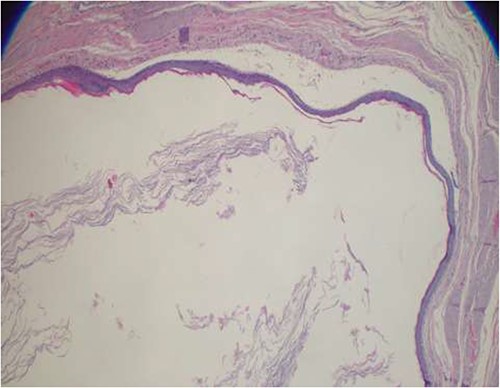

The patient underwent an en bloc surgical excision of the perineal mass together with the overlying skin (Figs 3 and 4) followed by primary closure of the wound (Fig. 5). The mass that weighed 228 g (Fig. 6) was removed and sent for histopathological evaluation, which confirmed the diagnosis of an epidermoid cyst as it consisted of stratified squamous epithelium that was lined with a granular layer with abundant keratin flakes (Fig. 7).

Photomicroscope highlighting a stratified squamous epithelial lining with a granular layer and abundant keratin flakes filling the cystic cavity (hematoxylin and eosin-stained sections, ×40 original magnification).

Histologically epidermoid cysts are lined by a stratified squamous epithelium containing a granular layer that is filled with keratin material. These features make the confirmatory diagnosis of an epidermoid cyst [5]. The aforementioned characteristics are in keeping with the histological finding in our case. Although large cysts have been linked to malignant transformation, the index case was benign.